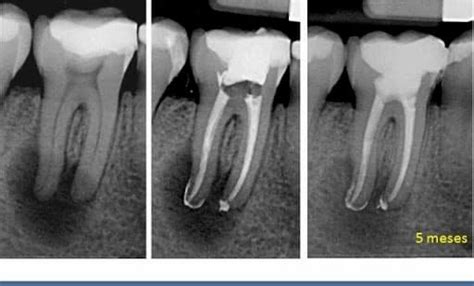

Radiografía de una endodoncia mal hecha

Una de las herramientas más seguras y fiables para detectar una endodoncia fracasada es la radiografía dental. En estas radiografías se pueden observar diferentes problemas:

- Sobreobturación: cuando el material de obturación se extiende más allá de la raíz, puede irritar los tejidos periapicales.

- Lesiones periapicales: se identifican como áreas más oscuras o radiotransparentes alrededor del ápice del diente. Lesión periapical: entre el 2 y el 14% de las endodoncias fracasan provocando inflamación periapical en los tejidos que rodean la raíz del diente.

- Conductos no tratados: puede que existan conductos adicionales sin tratar, los cuales aparecen como áreas radiotransparentes, ya que no han sido limpiados ni rellenados. No haber localizado un conducto. Cada diente tiene un número de conductos o nervios, y deben eliminarse y sellarse todos ellos. Aunque anatómicamente un molar suele tener tres conductos, existen casos en los que pueden tener cuatro e incluso cinco.

- Fracturas radiculares: aunque a veces son difíciles de detectar, pueden verse como líneas finas y oscuras a lo largo de la raíz. Existencia de una fisura o fractura vertical del diente. Muchas veces la endodoncia está bien hecha. Pero es posible que el diente tenga una fisura o una fractura dificil de diagnosticar, incluso con radiografías.